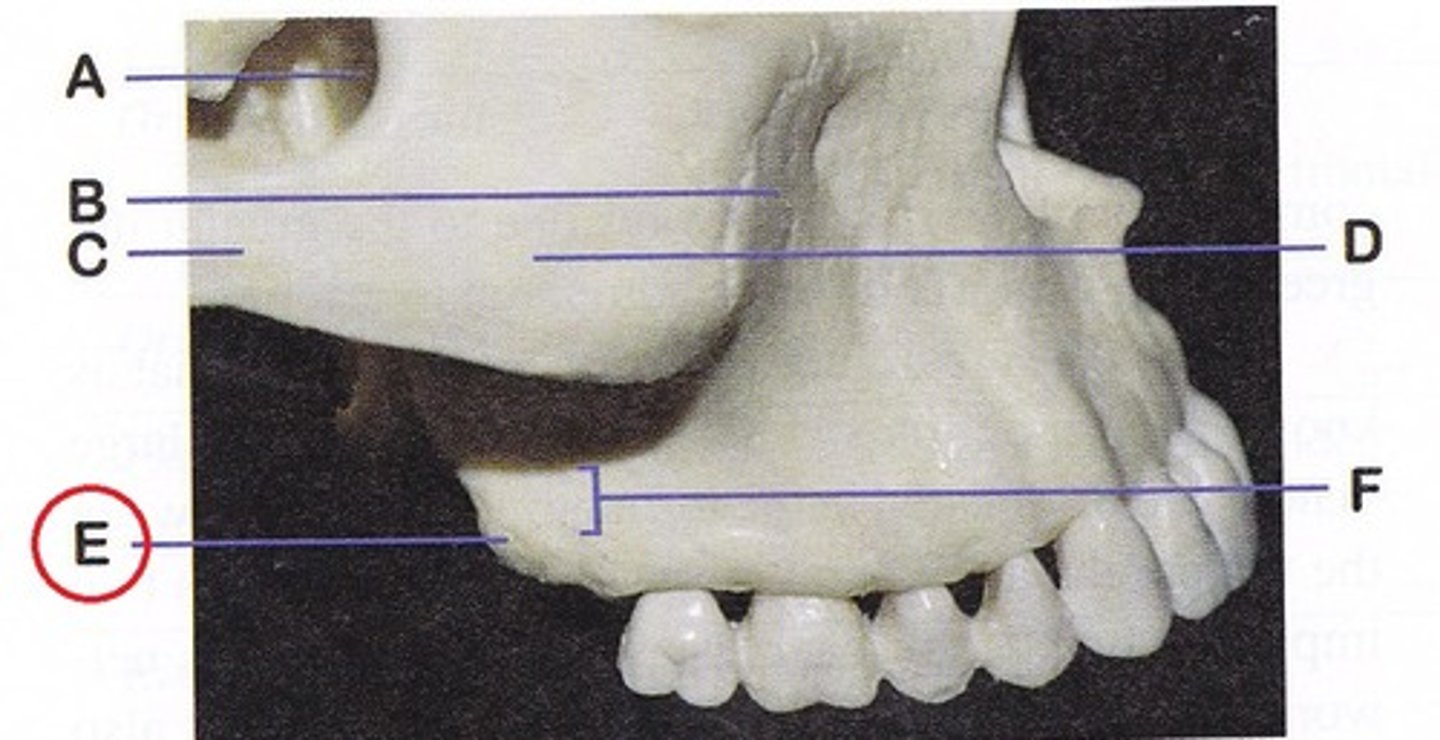

coronoid process ( anterior)

what is this

Mandibular notch

- between coronoid process and condyloid process

- forms lower part of Y

condyloid process ( posterior)

- makes up TMJ